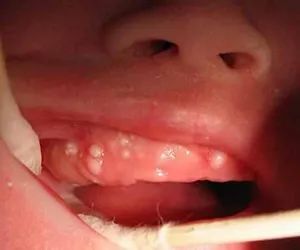

口腔內(nèi)有白點(diǎn)(馬牙、上皮珠)

在新生寶寶口腔的上腭中線附近會(huì)看到針頭或米粒大小的灰白色小點(diǎn),叫上皮珠,上皮珠是細(xì)胞脫落不完全所致。

在寶寶牙齒牙齦邊緣也會(huì)有白色小珠或灰白色硬塊,看起來好像萌出的牙齒,俗稱“板牙”或“馬牙”。

上皮珠和馬牙對寶寶沒有不良影響,不必做處理,會(huì)自然消失哦~